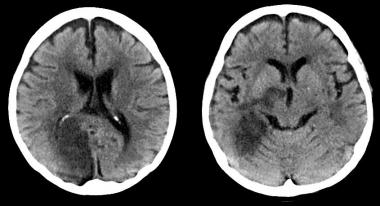

Efectos cerebrales del control intensivo de la hipertensión arterial

15 agosto 2019

En un subestudio del SPRINT se encuentra que los niveles más bajos de presión arterial se asociaron a una pequeña disminución de lesiones de la sustancia blanca, de significación clínica incierta. JAMA 13 de agosto de 2019